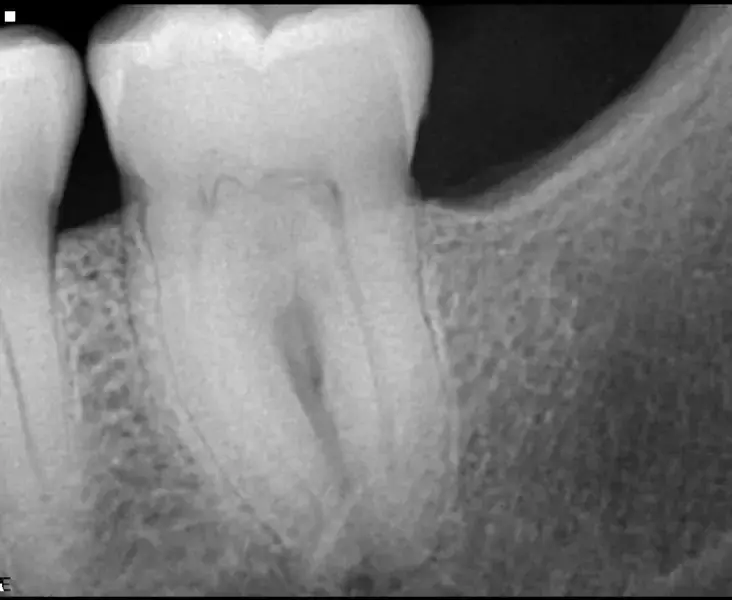

Пациент постъпва по спешност поради остра болка във втори горен молар. Това беше потвърдено при клиничния преглед. Направена е стандартна рентгенография (фиг. 1), която показва много сложна анатомия и калцирана пулпна камера. Историята на този зъб по думите на пациента е, че на него е бил поставен инлей, известно време след което се е появил дискомфорт, който е продължил няколко години без лечение. При контролния преглед му е било казано, че всичко е наред.

Фиг. 1 Предоперативна рентгенография, показваща много сложна кореноканална система и калцирана пулпна камера.